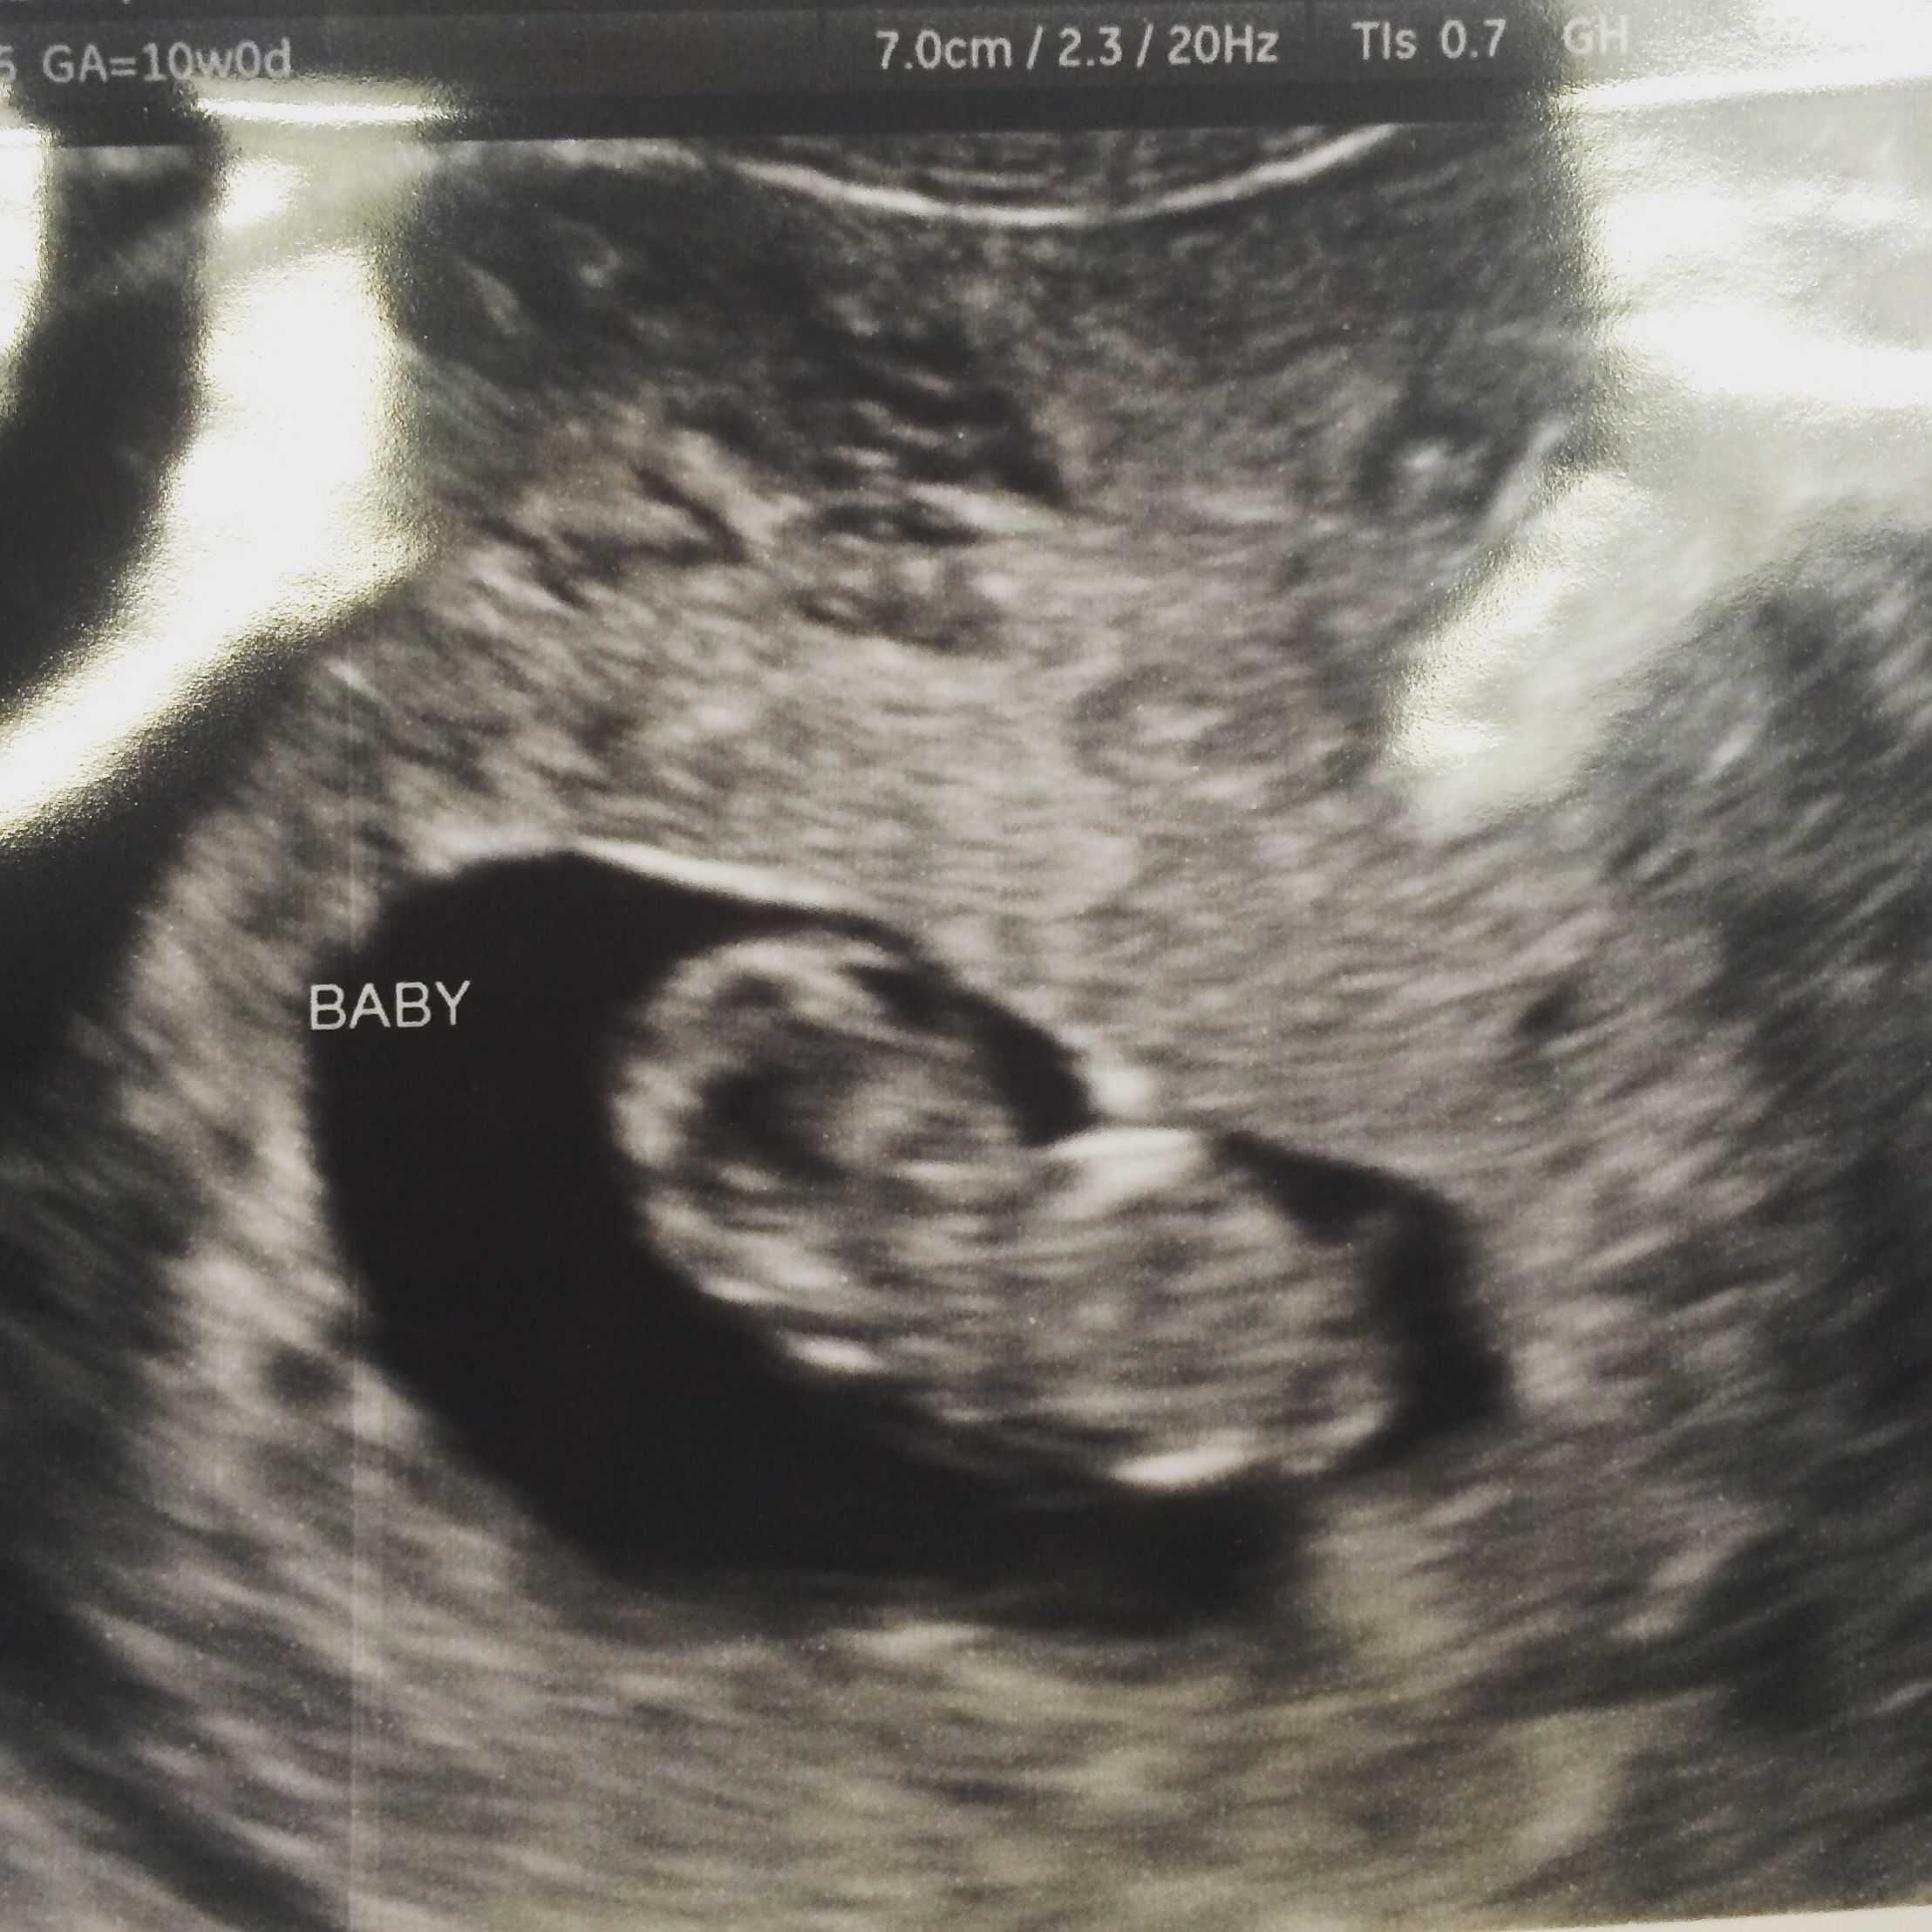

Finally got to see our peanut.

image